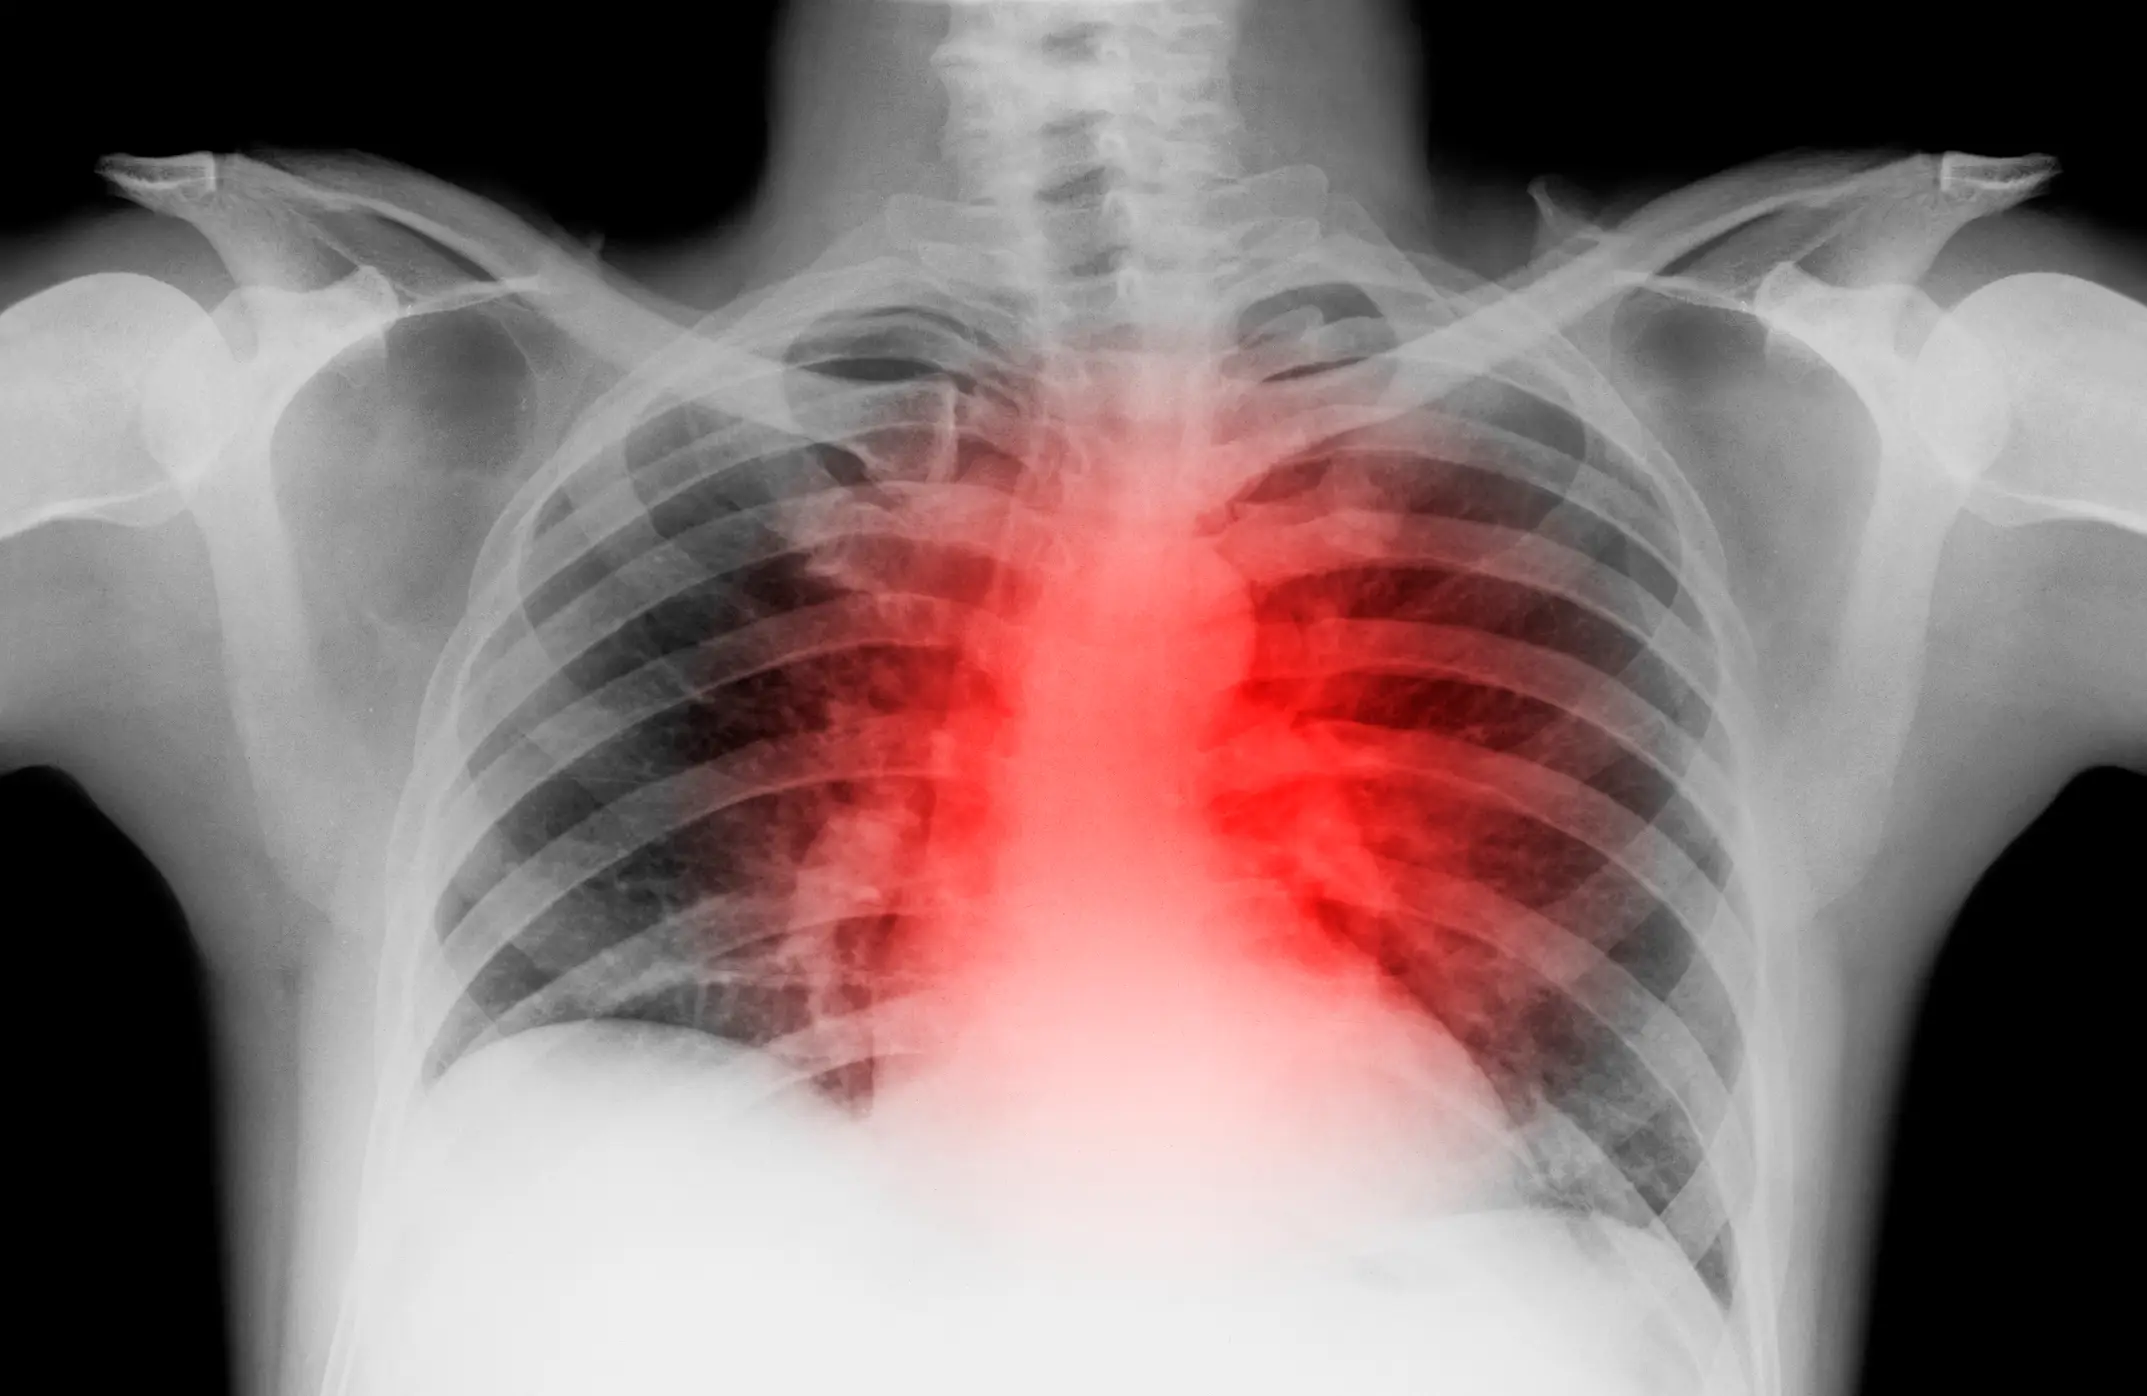

In more serious cases, it can lead to kidney or liver problems, heart attacks, or even strokes.